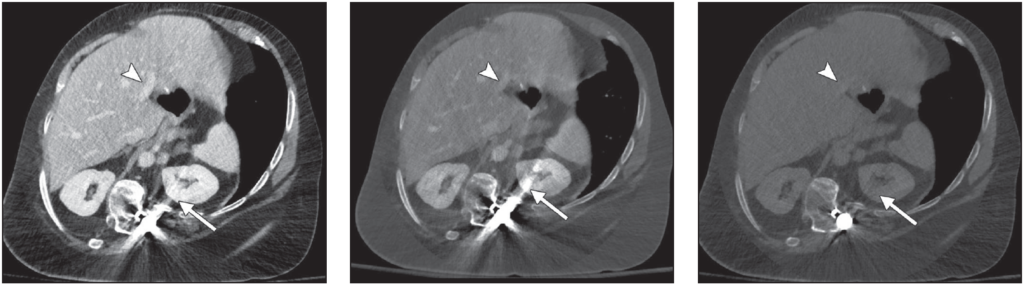

Portal venous phase abdominal CT images obtained after spinal reconstruction surgery. Left, Normal blended image shows considerable amount of metal artifact (arrow) overlaying left kidney and good contrast in portal veins (arrowhead). Center, Virtual monoenergetic image of same slice shown in Left, obtained at 50 keV, shows high portal venous contrast (arrowhead) and high amounts of metal artifact (arrow).Right, Virtual monoenergetic image of same slice shown in Left, obtained at 150 keV, reveals decreasing amounts of metal artifact (arrow) and loss of portal venous contrast (arrowhead).